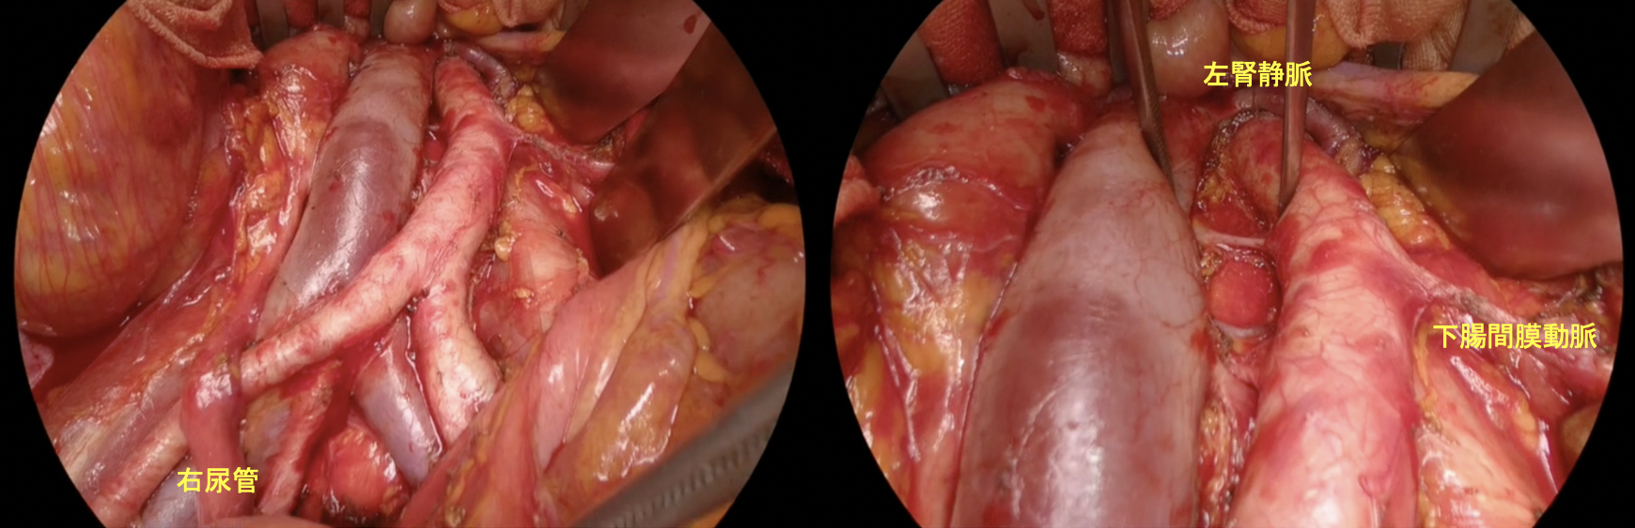

当院は腹腔鏡、ロボット手術の施設認定を取得しており、子宮筋腫や良性卵巣腫瘍の手術は極力腹腔鏡下の手術を行うようにしています。徳島県内では腹腔鏡手術の施行率はトップレベルで、腹腔鏡手術の技術認定医の取得を希望する若手の先生にとっては研修を行うには環境は整っていると考えます。最近では子宮脱に対するロボット支援下仙骨膣固定術も導入して、新しい術式にも挑戦しています。

悪性腫瘍の治療も症例数は増加しています。子宮頸癌に対する広汎子宮全摘術や、若年症例に対して子宮を温存する広汎子宮頸部切除の手術を行うことも可能です。また子宮体癌の手術では、腹腔鏡下に行う手術に加えて、2025年2月から、ロボット支援下子宮悪性腫瘍手術も導入しました。また卵巣癌の症例に関しても、積極的な手術を展開しています。その一方で、機能温存治療としての子宮頸部上皮内腫瘍に対するLEEP切除やレーザー蒸散、若年子宮体癌に対するホルモン療法などの治療を導入しており、症例数も増加しています。婦人科癌に対する薬物療法は免疫チェックポイント阻害薬が導入され、目覚ましい進歩がありますが、最新の治療が受けられる体制を準備して治療にあたっています。当院は婦人科癌に対しては全国トップレベルの治療が行える施設と考えています。